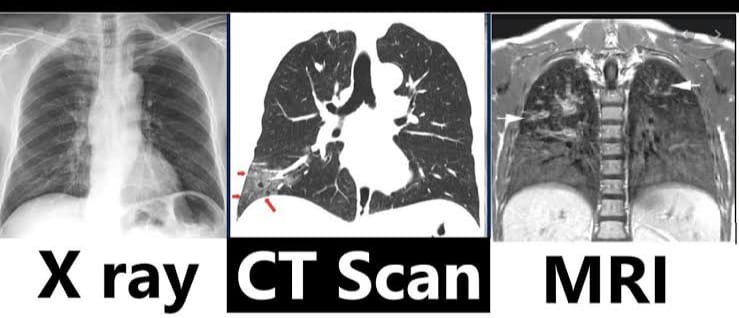

Imaging studies (ઇમેજિંગ સ્ટડીસ):

- ઇમેજિંગ સ્ટડી એ એનાટોમિક સ્ટ્રક્ચરને ઇવાલ્યુએટ કરવા માટે કરવામાં આવે છે.

- જેમાં એક્સરે, સીટી સ્કેન, એમ. આર. આઇ, એન્જિયોગ્રાફી અને વેન્ટિલેશન પરફ્યુઝન લંગ સ્કેનનો સમાવેશ થાય છે.

Chest x-ray (ચેસ્ટ એક્સરે):

- ચેસ્ટ એક્સરે માં સ્મોલ અમાઉન્ટ એકસ રેનો ઉપયોગ કરીને તે એરિયાનો 2D ઇમેજ ક્રિએટ કરવામાં આવે છે અને તેમાં બોન અને ટ્યુમરને વિઝયુલાઈઝ કરી શકાય છે.

- તેમાં મુખ્યત્વે એન્ટેરિયર-પોસ્ટેરીયર અને લેટરલ સાઈડનો વ્યુ લેવામાં આવે છે.

- એક્સ રે કરતા પહેલા પેશન્ટને ફૂલી ઇન્સ્પિરેશન કરવાનું કહેવામાં આવે છે તેથી લંગને સારી રીતે વિઝયુલાઇઝ કરી શકાય.

- એક્સ રેની મદદથી ન્યુમોનિયા, લંગ કેન્સર, ટ્યુમર, ફોરેન બોડી તેમજ રિબ્સ ફેક્ચરને આઇડેન્ટીફાય કરી શકાય છે.

CT-scan (સીટી સ્કેન):

- સીટી સ્કેન એ એકસ રે કરતા વધારે ડિટેઈલમાં માહિતી આપતું અને થ્રીડી ઇમેજ પૂરું પાડતું ઈમેજિંગ સ્ટડી છે.

- સીટી સ્કેનમાં બોડીના જુદા જુદા એન્ગલ થી એક્સ રે લેવામાં આવે છે અને કમ્પ્યુટરની મદદથી બોડીના ક્રોસસેક્શન પિક્ચરને ક્રિએટ કરવામાં આવે છે.

- સીટી સ્કેનની મદદથી ઓર્ગન અને સોફ્ટ ટીસ્યુની કન્ડિશન જાણી શકાય છે.

- સીટી સ્કેનથી લંગ કૅન્સર, પલ્મોનરી એમ્બોલિઝમ અને ઇન્ફેક્શન આઈડેન્ટીફાઇ કરી શકાય છે.

MRI (એમ. આર. આઇ):

- MRI – મેગ્નેટિક રેઝોનન્સ ઇમેજિંગ

- MRI માં પાવરફુલ મેગ્નેટ અને રેડિયો વેવ્સ નો ઉપયોગ કરવામાં આવે છે અને આપેલ એરિયાનો ક્રોસસેક્શન ઈમેજ ક્રિએટ કરવામાં આવે છે.

- MRI એ હાર્ટ, લંગ અને બ્લડ વેસેલ્સની ડિટેલમાં ઇન્ફોર્મેશન પૂરી પાડે છે.

- MRI ની મદદથી પલ્મોનરી નોડયુલ્સ, ફાયબ્રોસિસ, પ્લુરલ ડીઝીસ અને વાસ્કયુલર એબનોર્મલીટીને ડિટેક્ટ કરી શકાય છે.